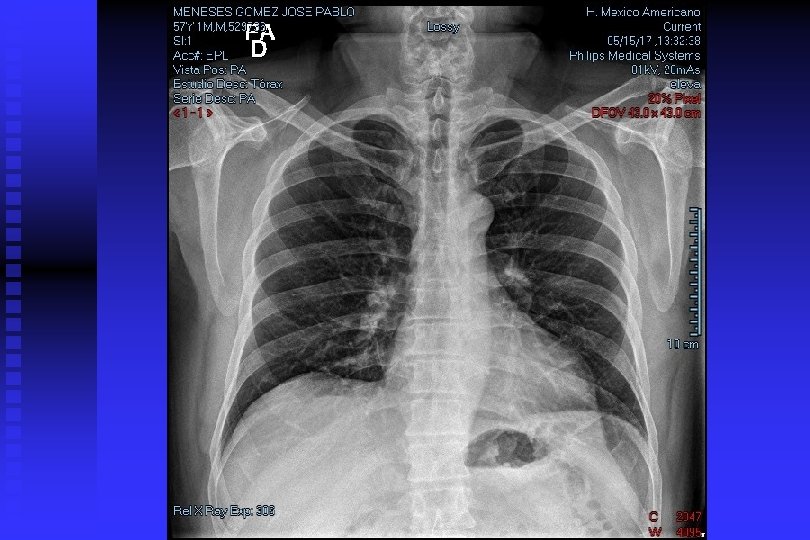

Cancer Pulmonar Rx de Tórax

DIAGNOSTICO DE CANCER PULMONAR RADIOGRAFIA DE TORAX: Permite descubrir CP en asintomáticos en 67 -82% y de estos el 24% tiene citología de esputo anormal. TOMOGRAFIA DE TORAX: Sensibilidad del 85% para CP y una especificidad del 95%. Per– mite descartar causas benignas de nódulos pulmonares con uni – dades Hounsfield >175= benigno; adenopatías <1 cm= benignos; 1 -2 cm= Indeterminado, >2 cm= positivo. Permite conocer actividad metastásica, y para estadificación (S= 73% y E= 80%).